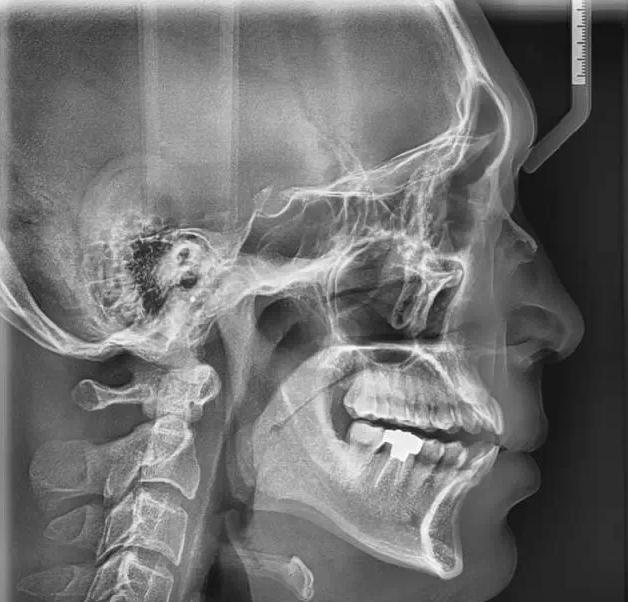

PaX-i 雙傳感器設備 |